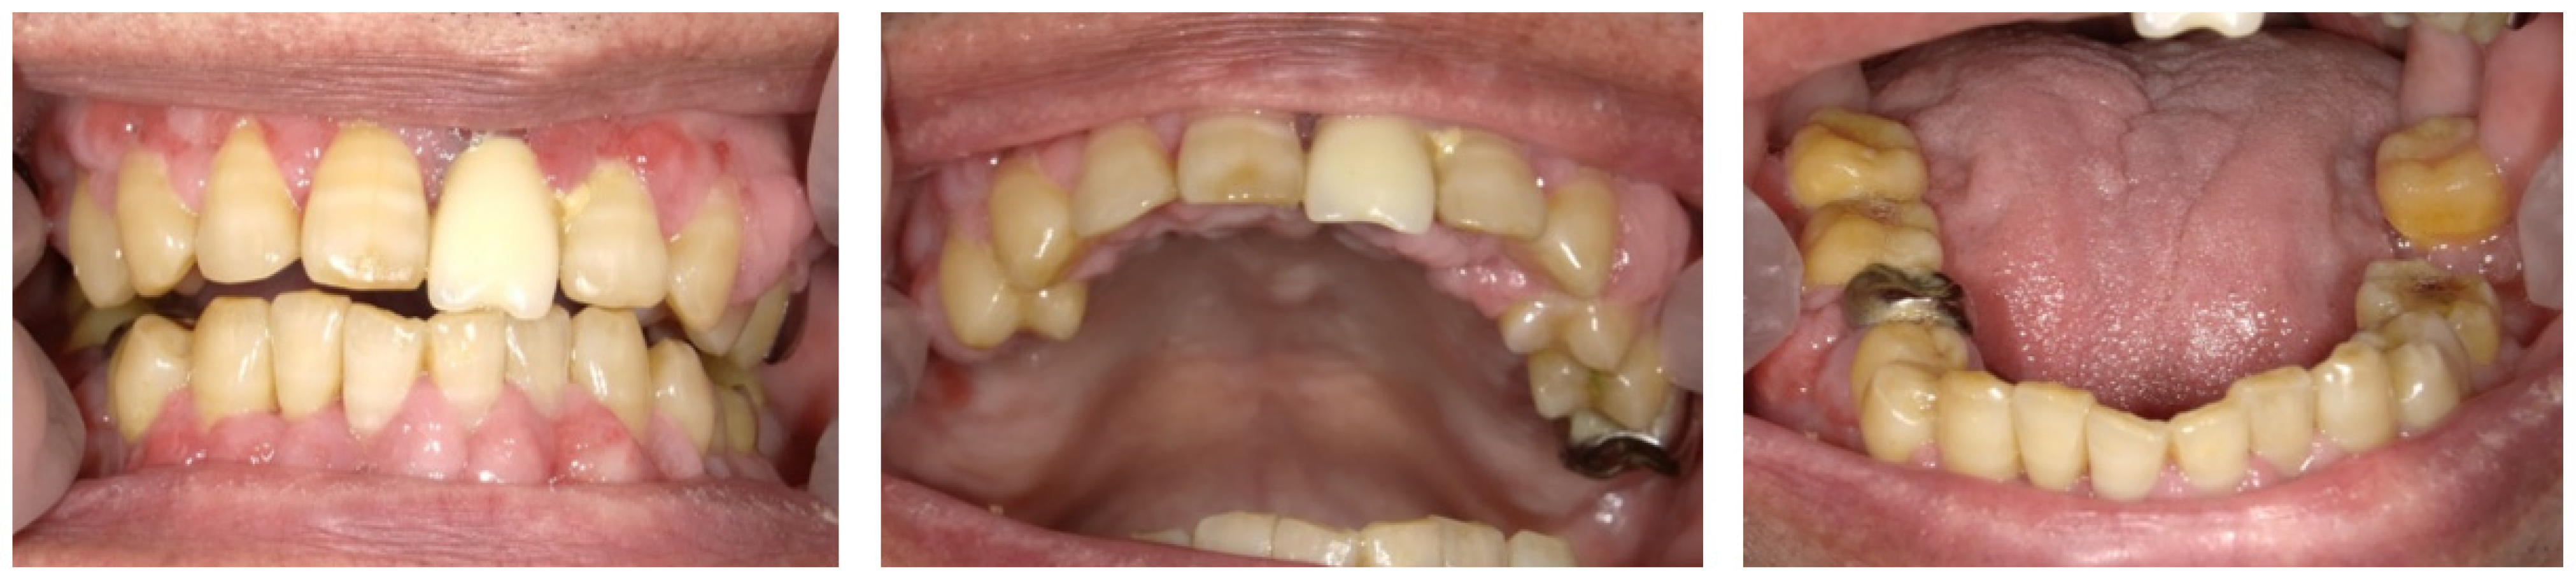

At the first examination, the patient’s gingiva showed generalized redness and bleeding with spontaneous pain (Figure 1). Prominent bleeding and discharge of suppuration were observed in the gingiva. The interdental papillae exhibited crater-shaped ulcerations. Severe oral halitosis was present. Physical examination findings were as follows: body temperature, 36.7 °C; blood pressure, 142/60 mmHg; and heart rate, 84 beats/min. The initial blood test indicated the following: white blood cell count, 6500/μL; platelet count, 22.8 × 104/μL, total protein (TP); 6.9 g/dL, C-reactive protein (CRP); 0.14 mg/dL, prothrombin time (PT), INR, 1.2; activated partial thromboplastin time (APTT), 40 s; and HbA1c, 6.0%.

Figure 1.

Intraoral photos taken at the patient’s first visit reveal generalized gingival redness, swelling, and bleeding.

The acute symptoms resolved on day 7 (Figure 2A). We conducted a periodontal examination, including an assessment of probing pocket depth (PPD) and bleeding on probing (BOP). Because our patient had difficulty undergoing extensive examinations, we evaluated the one-point PPD instead of the six-point PPD (Figure 2B). Panoramic radiography was also performed (Figure 2C). During the periodontal examination, the entire circumference of each tooth was explored using the walking probe technique, and the value of the deepest pocket was recorded as representative of that tooth. In 11 teeth, PPD ≥ 4 mm with bleeding was detected. Of these, seven had deep pockets of >6 mm (Figure 2B). Panoramic radiography revealed a horizontal absorption of the entire alveolar bone (Figure 2C). On the basis of these comprehensive findings, NP was confirmed as the final diagnosis. Our patient also met the transiently and moderately compromised status criteria in the 2018 classification of NPD.

Figure 2.

The findings at 7 days after the first visit. (A) These intraoral photos show that the acute symptoms, including redness, swelling, and bleeding, have decreased. (B) Periodontal assessment includes tooth mobility (Mobility), bleeding of probing (BOP), and probing pocket depth (PPD) (maximum value on each tooth). Black color boxes indicate missing teeth. The green color box indicates acceptable PPD (not exceeding 3 mm). Yellow color boxes indicate PPD of 4 or 5 mm. Orange color boxes indicate PPD equal to or greater than 6 mm. BOP (−) indicates no bleeding. BOP (+) indicates bleeding. (C) Panoramic X-ray reveals that the entire alveolar bone has horizontal absorption.